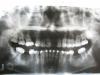

Чиффа Опубликовано 12 февраля, 2010 Поделиться Опубликовано 12 февраля, 2010 http://forum.stom.ru/index.php?showtopic=4655 почитайте правила.хотя бы панорамный снимок разместите Ссылка на комментарий

Sa6a Опубликовано 12 февраля, 2010 Автор Поделиться Опубликовано 12 февраля, 2010 Ну, раз уж размещаю фото, то, если можно, прокомментируйте пожалуйста ситуацию в целом.Насчет лица - в каком направлении собственно оно должно меняться?По поводу "вечного ничего нет" - спасибо конечно, но вопрос был не об этом.Хотелось бы также примерно представлять среднюю стоимость ортодонтического лечения (Москва, обычная частная клиника). Ссылка на комментарий

Sa6a Опубликовано 13 февраля, 2010 Автор Поделиться Опубликовано 13 февраля, 2010 А что с верхней челюстью? В особенности с промежутком в левой части снимка. Что касается нижних шестерок - ортодонт-консультант предлагает не имплантацию, а какую-то конструкцию, опирающуюся на шестерки и пятерки. Это нормально? Удаление восьмерок - это вещь обязательная или они не мешают? Ссылка на комментарий

irenika Опубликовано 13 февраля, 2010 Поделиться Опубликовано 13 февраля, 2010 А что с верхней челюстью? В особенности с промежутком в левой части снимка. Что касается нижних шестерок - ортодонт-консультант предлагает не имплантацию, а какую-то конструкцию, опирающуюся на шестерки и пятерки. Это нормально?Удаление восьмерок - это вещь обязательная или они не мешают? промежуток между 6 и 4(вроде это он или 3???)-с одной стороны вроде быстрее и "дешевле"закрыть перемещением 6 к 4 и изменить форму 4 на форму клыка.но!у вас опять-таки,нет вообще премоляров с этой стороны!а с противоположной полный комплект.по ОПТГ невозможно решить каким образом тут поступить.промежуток от 1-однозначно имплант. что там за конструкцию решает ваш ортодонт на нижнем зубном ряду не поняла. Ссылка на комментарий

Sa6a Опубликовано 13 февраля, 2010 Автор Поделиться Опубликовано 13 февраля, 2010 промежуток между 6 и 4(вроде это он или 3???)-с одной стороны вроде быстрее и "дешевле"закрыть перемещением 6 к 4 и изменить форму 4 на форму клыка.но!у вас опять-таки,нет вообще премоляров с этой стороны!а с противоположной полный комплект.по ОПТГ невозможно решить каким образом тут поступить.промежуток от 1-однозначно имплант. что там за конструкцию решает ваш ортодонт на нижнем зубном ряду не поняла. Премоляры были на месте промежутка. Не совсем понял, перемещение 6,7, и 8 вперед возможно? Или отсутствие премоляров чем-то нехорошим может закончится?Тройка - это клык. Форма у него такая - я в детстве все время им проволоку перегрызал.Что ему нужно еще какую-то форму придавать? Что касается нижней челюсти - я так понял конструкция типа моста, это для того, чтобы семерки не наклонялись в сторону отсутствующих шестерок. Если ставить имплант - в этом случае надо будет один гвоздик, или по числу корней? Ссылка на комментарий